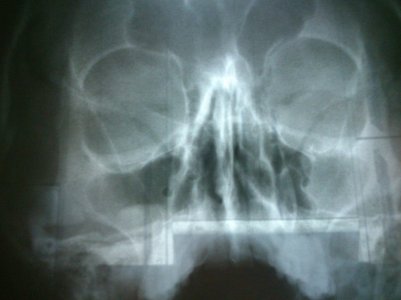

Здравствуйте. Помогите пожалуйста разобраться. С левой стороны под глазом на скуле ,появился отек,не большого размера ,округлой формы.не проходит уже месяц,с утра более выражен к вечеру как-будто меньше.боль в височной области бывает и контрактура жевательной мышцы на этой стороне..нос не заложен,выделений нет,температуры нет,пальпация в области гайморовой пазухи безболезненна ,отсутствует боль при наклоне головы вперёд,иногда незначительная боль в области гайморовой пазухи присутствует.был сделан снимок,на котором видно полное затемнение пазухи. Врач сказал что это киста ,нужно ждать консультацию лор врача,а она только в сентябре. Возможно ли что это обычный отек слизистой или киста или что то серьезное ? В прошлом я болела гайморитом и полип этой пазухи был,лечила спреем бекло-рино или альдецин.

DSC_0118.jpgг

Ответ: Дорогая lio, причин для такого явления может быть много (киста, воспалительный процесс, опухоль и т.д.) и каждая требует своего лечения, которое подбирает лор-специалист при осмотре. По Вашей истории, похоже на обострение хронического полипозного гайморита с разрушением кости, что требует срочного хирургического вмешательства.

Ответ :дорогой аирсильвер,пробыла по ургенции в госпитале целый день и получила консультацию двух специалистов-радиолога и лор врача .со стороны врача радиолога-затемнение двух пазух без пат.включений.....осмотр лор врача -с помощью эндоскопического зонда и зеркал-патологий не обнаружено -ни полипов ,ни кисты....даже соплей нет.....затемнение на снимке результат ранее перенесенного заболевания .МДА..разрушение кости-:-) :-) :-) :-) :-) :-) :-) ктоб подумал такое написать! Зато благодаря вашему дикому предположению я зашевелилась быстрее и все